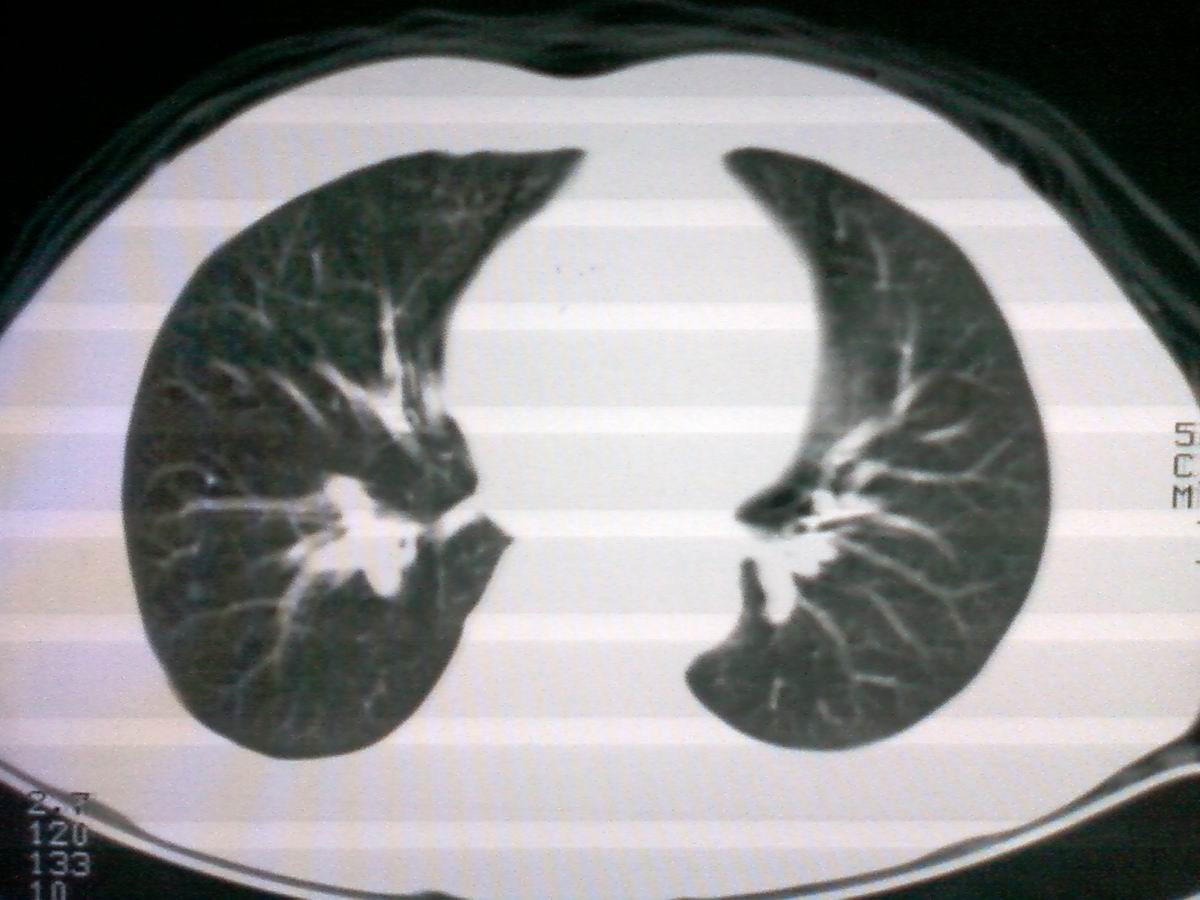

标题: CT25801:患者男性,65岁,临床提示双肺可闻及广泛罗音,看 [打印本页]

标题: CT25801:患者男性,65岁,临床提示双肺可闻及广泛罗音,看

仅见肺纹理影增重 纵膈淋巴结钙化